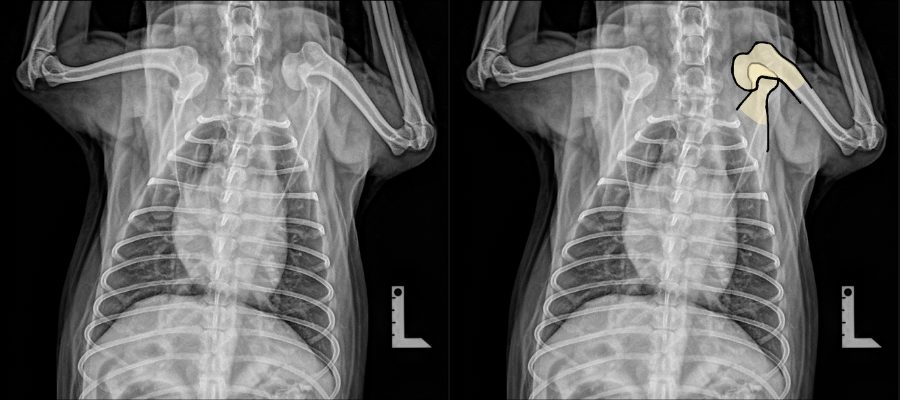

<術前のレントゲン>

左肩関節が内側に脱臼しています。

(正面像)